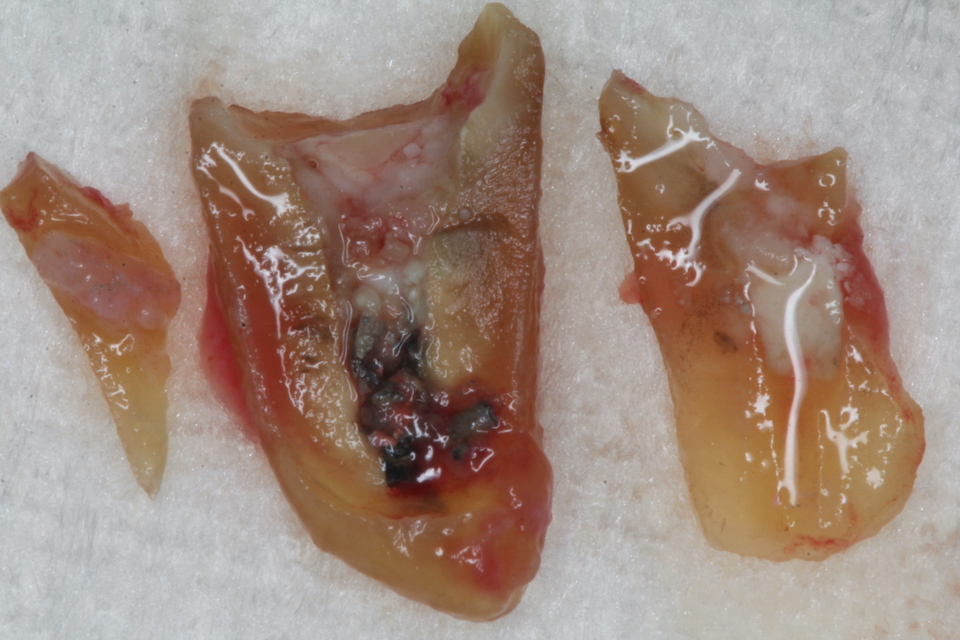

今日の抜歯再植術シリーズ34.2

60代女性、左下6、歯根破折、GA前回のつづきhttps://plaza.rakuten.co.jp/mabo400dc/diary/202505180000/もう便宜的に抜歯して再建して再植するというのはかれこれ25年以上30年近くやっています。最初は抜歯してインプラントという選択肢もあったのですが、当地にUターンして開業してからはインプラントは一件もしていません。理由を考えてみたのですが、抜歯したところに再建した歯を戻すだけですから、簡単でインプラントと予後も変わらないと思ったからです。インプラントは打ちたいところと打たねばならない場所が異なることがままあり、全ての症例に対応できないというのが最も大きい問題点でした。今日は再建して再植まででは時系列でどうぞ3つに割れていたが、一番大きな破片が問題。ピンク色の根管充填材の周りは黒い。細菌の代謝産物の硫化鉄、細菌が入り放題だったようだ。根管充填材を除去すると根尖口が見える。これを充填しないと再発する。穴を開拡する大きく開拡した。全部の破片を綺麗にしたが、別の穴が見つかった。これは別の根管と根尖口でこれも埋めないと再発する。根管は1本だけではなく何本もあるので、見逃すこともあるし、根管治療が上手くいくわけでもない。最初から神経など取らないのがベストだ。2本目の根管も綺麗にして開拡しておく。2番目に大きな破片を張り合わせた。3個目の破片も張り合わせた。ポストを入れて歯冠部を修復。コア状で良い。接着剤がちゃんと入っているか確認する。洗浄した抜歯窩に再建した歯根を挿入固定する。包帯して投薬4日。その頃包帯は除去する。

今日の抜歯再植術シリーズ34.1

60代女性、左下6、歯根破折、GA前回のつづきなんですが、2年程前に同じ症状が出た時の画像を探したのでご供覧。https://plaza.rakuten.co.jp/mabo400dc/diary/202505170000/すでに何年も前からクラックが入っていたり、神経は取ってあるものの根管が緊密に根管充填されていなかったり、根尖口が閉鎖していなかったり、そもそも冠やメタルコアのセメント合着が効いていなくて隙間だらけで硫酸塩還元細菌の住処となっていたりとどうしようもない状況になっていたわけです。こういうことは通常の歯科治療では普通のことだと思っても良いと思います。要するに歯科治療は上手くいくことの方が稀なので、してはいけない!どんな方法を採っても、技術的に優れた術者が行ってもです。特に神経を取る治療は歯の寿命が30年位になるというのが本当のところです。まあ、30年も持つのなら患者も何時何処の歯医者でやったかも忘れているだけのお話というお寒い現状が実態です。人生50年、60まで生きれば御の字の時代ならよかったのですが、今はそうではない。このサイトではどうすれば神経を取らずに歯の寿命を伸ばすことができるか?という誰でもできる方法を無料公開していますので全部ご覧ください。記事がたくさんあるので大変でしょうが、まぁ、少なくとも高校卒業程度の物理化学生物の基礎知識は必要です。では時系列でどうぞ腫れている冠を除去冠もコアも歯根内部も真っ黒。硫酸塩還元細菌の代謝産物(うんこ)のFeS(硫化鉄)にまみれている。細菌が繁殖できる隙間があったということで、セメント(接着剤)合着系の修復物には多かれ少なかれ普通にあることです。クラックがありすでに割れているということが分かる。つづく

今日の抜歯再植術シリーズ34.0

60代女性、左下6、歯根破折、GA久しぶりの再植ネタというか臨床ネタだ。数年前も腫れて歯根にクラックが入っているのを確認していた。当時の画像があったらアップしてみたい。まずはレントゲン写真でのbefore/afterからbefore黄色矢印に囲まれた部分が肉芽というか膿瘍というか、大きな炎症性組織がある部分。after腫れている遠心根のみ分割抜歯の予定。冠が外れると歯根が割れているのが見える。歯根端に大きな膿瘍が付着していて、ズルズルと一緒に抜けてくる。膿瘍を掻爬して3MIX+生食水で洗浄しておく。両隣に維持溝を掘っておく。膿瘍はハサミで切除し、破片を合わせてみた。割れた歯根は3ピースだ。つづく